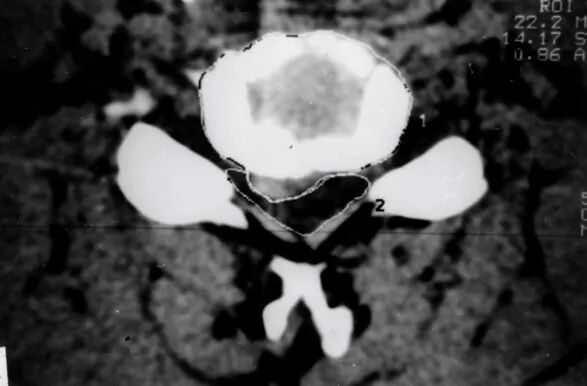

CT扫描从颈椎横断切层显示椎管、脊髓及其相互关系

颈椎病CT表现